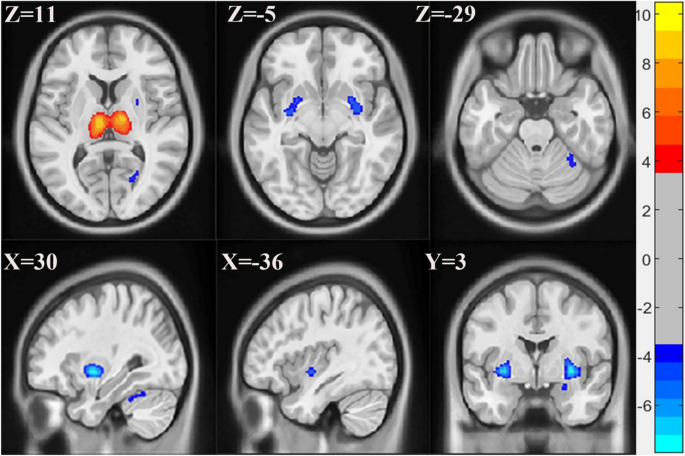

Based on the MDL criterion, the grey matter images of all participants were decomposed into 4 components (Supplementary Fig. 1). All 4 components were stable with no artifacts. Among the 4 components, only component 4 showed significant differences in loading coefficients between FM patients and HC subjects. The patient group showed higher loading coefficients in this component than the HC group (component 4: t = 6.9932, FDR corrected P = 0.0002). Components 1, 2, and 3 did not show significant loading coefficients between the 2 groups (component 1: t = − 1.22, P = 0.22627; component 2: t = 0.71446, P = 0.47931; component 3: t = − 0.53863, P = 0.59328). However, the interpretation of loading coefficients depends on the sign of the corresponding spatial map. For instance, if the FM group has higher loading coefficients than the HC group for a component with a predominantly positive spatial map, the FM group exhibits greater tissue volume in this pattern. Conversely, a predominantly negative spatial map indicates rather lower tissue volume in the FM group. The significant component (component 4) representing distinct grey matter regions between the two groups was threshold at |Z|> 3 (Fig. 1). Specifically, the bilateral thalamus showed greater GMV in the FM group while lower GMV in the right cerebellum lobule 6, bilateral putamen, bilateral pallidum, bilateral insula, right amygdala, right hippocampus, and the right calcarine were observed in the FM group. Detailed information about these brain regions is presented in Supplementary Table 1. The insignificant components maps were also threshold at |Z|> 3. Component 1 mainly showed greater GMV in the cerebellum of FM patients compared to HC subjects (Supplementary Fig. 2 and Supplementary Table 2). Component 2 exhibited greater GMV in the bilateral thalamus in FM compared to HC subjects (Supplementary Fig. 3 and Supplementary Table 3). In component 3, the bilateral temporal middle pole, the right hippocampus, left putamen, right fusiform, and left inferior temporal gyrus showed greater GMV in FM patients whiles the right cerebellum lobules 6 and 8 showed lower GMV in FM patients (Supplementary Fig. 4 and Supplementary Table 4).

Spatial maps of component 4 showing significant GMV differences between FM patients and HC subjects. Hot (Red) colour represents greater GMV in FM and blue colour represents lower GMV in FM. FDR corrected P < 0.001. Spatial maps were shown with a threshold of |Z|> 3. FM, fibromyalgia; HC, healthy control; GMV, grey matter volume; FDR, false discovery rate.